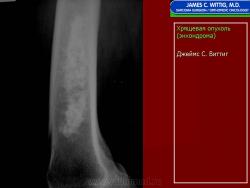

Энхондрома (син.: хондрома, центральная хондрома) — доброкачественная хрящевая опухоль, расположенная в костномозговом канале (интрамедуллярно). Встречается в 10 % случаев от общего числа доброкачественных опухолей костей. Считается, что она возникает из эктопически расположенных островков хряща, отщепившегося от пластинки роста на ранних этапах онтогенеза. В ряде случаев опухоль остается бессимптомной и обнаруживается случайно при рентгенологическом исследовании. В других случаях возникают боль и припухлость. Обычно болезненными становятся все энхондромы фаланг. Наиболее частая локализация: фаланги, главным образом, пальцев кистей, проксимальный конец плечевой кости, проксимальный или дистальный концы бедренной кости. При рентгенологическом исследовании в энхондроме определяются просветления с участками минерализации. Тень кости становится более широкой, кортикальный слой сохраняет целостность, но истончается. В редких случаях энхондрома имеет вид эксцентрически растущего экзофитного новообразования. Макроскопически опухоль представляет собой голубовато-белую полупрозрачную хрящевую ткань, в которую вкраплены желтоватые участки обызвествления. Опухоль состоит из отдельных хрящевых узелков, диаметр которых варьирует в пределах 1 см.

Рентгенологическая картина хондромы представляет четко очерченный опухолевый узел. Очаги минерализации в хондромах выглядят достаточно характерно и представлены очаговыми, глыбчатыми или кольцевидными , арочными отложениями извести. Полного разрушения кортикального слоя трубчатой кости с выходом опухолевых масс в мягкие ткани не наблюдается.